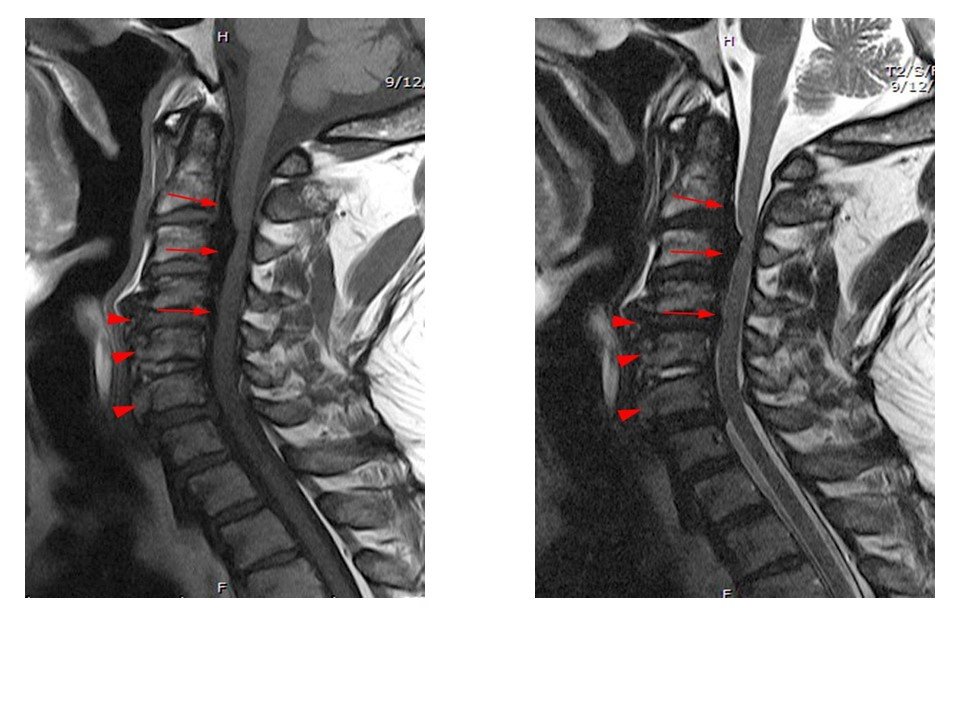

A 64-year-old man developed neck pain after falling off a truck one week ago. T1- and T2-weighted sagittal MR images (1 and 2) are provided. What are the findings? What is your diagnosis?

An extensive low signal intensity epidural abnormality posterior to the vertebral bodies and discs from C2 through C6 (arrows) produces spinal stenosis, most severe at C3, where there is resultant cord compression and faint T2 cord signal hyperintensity. Ossifications are present anterior to the vertebral bodies and discs (arrowheads).

Thick ossification is present posterior to the vertebral bodies and discs corresponding to the MR low signal intensity (arrows). Flowing ossification is present along the anterior vertebral bodies and discs (arrowheads).

ANSWER-

Ossification of the posterior longitudinal ligament (OPLL), continuous type, producing spinal stenosis, cord compression and edema. Diffuse idiopathic skeletal hyperostosis (DISH) is also present.